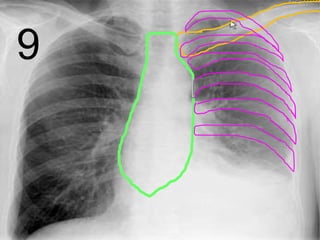

• Your skeletal system surrounds your most

important internal organs with a rib cage.

Copyright © 2010 Ryan P. Murphy